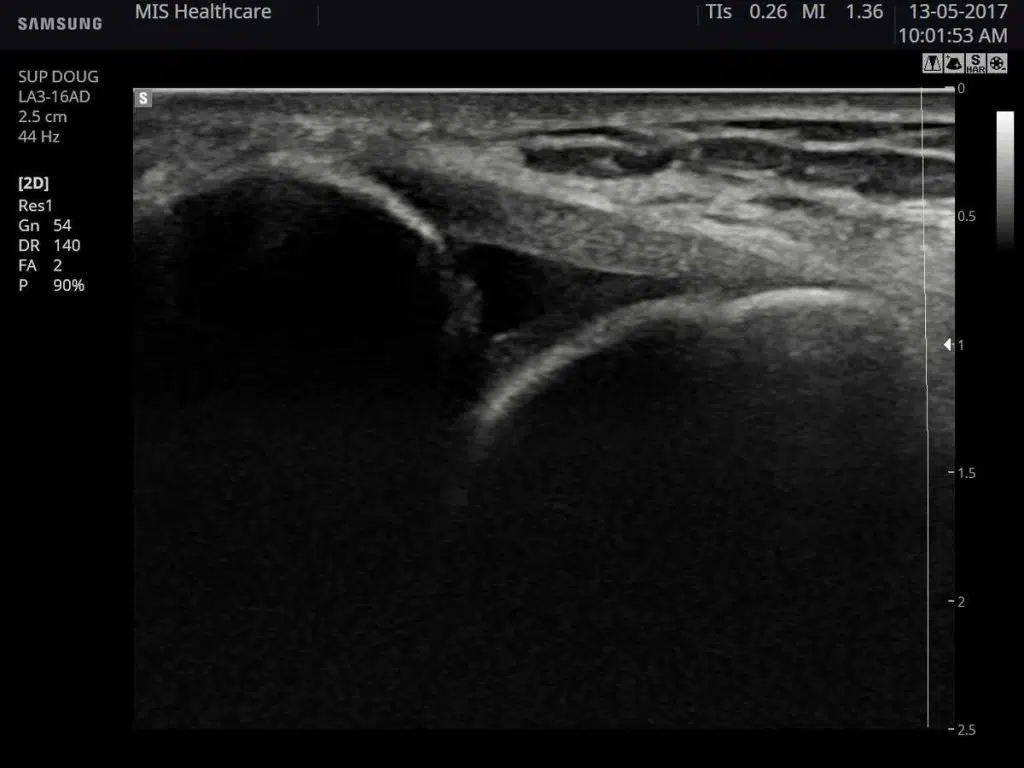

Samsung HS40 Ultrasound Machine. Samsung HS40 is an economy multi-purpose diagnostic ultrasound system designed to cover a vast range of applications such as obstetrics, stomach, gynecology, pediatric, little organs, including neonatal cephalic, mature cephalic, trans-rectal, trans-vaginal, MSK (standard, superficial), urology, adult cardiac, and peripheral vessel.

Samsung HS40 is an economy multi-purpose diagnostic ultrasound system designed to cover a vast range of applications such as obstetrics, stomach, gynecology, pediatric, little organs, including neonatal cephalic, mature cephalic, trans-rectal, trans-vaginal, MSK (standard, superficial), urology, adult cardiac, and peripheral vessel.

It features advanced imaging technologies to help you achieve clear and detailed images. Unlike other brands, this minimizes signal noise so that you can concentrate on the patient without disruptions. Samsung hs40 contains all the necessary tools to enhance your workflow.

Thanks to the enhancement of ultrasound technology, you can achieve high resolution in sonography. Samsung hs40 contains this crucial feature which enhances diagnostic accuracy through visualizing tissue elasticity. It can detect tissue stiffness and covert this into clear images.

Linear probe LA3-16AD